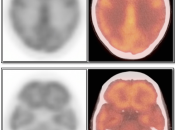

- Characterizing lesions as “low-grade” or “high-grade” (with dramatic implications on management & prognosis):

- Low-Grade: Uptake ≈ white matter (may use contralateral centrum semiovale for comparison)

- High-Grade: Uptake > white matter (≈ grey matter)

Radiation Necrosis (or Chemonecrosis):

- Necrosis presents months to years after radiation therapy (rarely < 3 months post radiation).

- Difficult to differentiate necrosis from malignancy on MRI, as both demonstrate enhancement.

- Necrosis is typically non-avid on PET images.

- Recurrent malignancy will demonstrate FDG uptake, often focal and involving only a small portion of a surgical cavity. The uptake may be intense (an easy diagnosis) or may be minimally above adjacent background uptake (a more difficult diagnosis, which may require follow-up).

- FDG-avid recurrence should correspond to the area of enhancement noted on MRI (MRI should be done first, with images available at time of PET/CT interpretation).

- If no evidence of pathologic uptake, we report, “There is no evidence of high-grade tumor recurrence.”